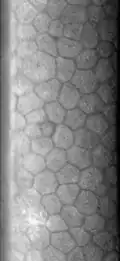

Эндотелий роговицы, задний эпителий роговицы — монослой специализированных плоских клеток, выстилающих заднюю поверхность роговицы и входящих в соприкосновение с содержимым передней камеры глаза. Гексагональные клетки эндотелия содержат повышенное количество митохондрий и осуществляют транспорт жидкости и растворенных веществ, поддерживая роговицу в слабо дегидрированном состоянии, необходимом для её прозрачности. Площадь клеток примерно одинакова; при значительном разбросе их размера говорят о наличии полимегетизма.

Изображение гексагональных клеток эндотелия роговицы при световой микроскопии в отражённом свете